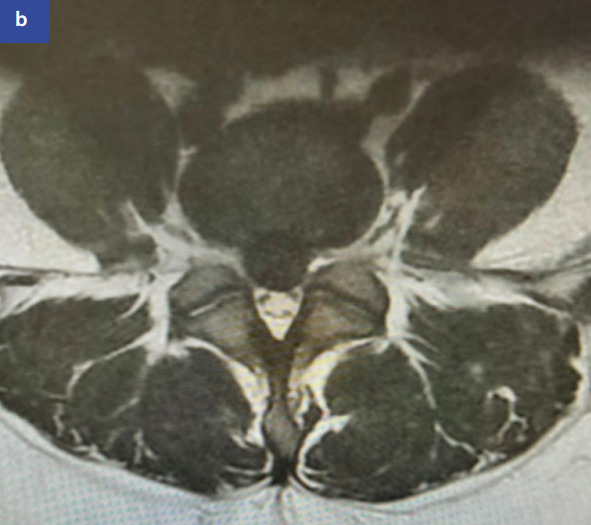

保守治疗目标为缓解症状,等待自然吸收(15-93%突出可缩小)。推荐早期活动、NSAIDs、理疗及心理干预。硬膜外注射(图5)可筛选手术候选者。

图5:腰椎磁共振成像矢状位(a)和轴位(b)显示腰4/腰5节段中央型椎间盘突出